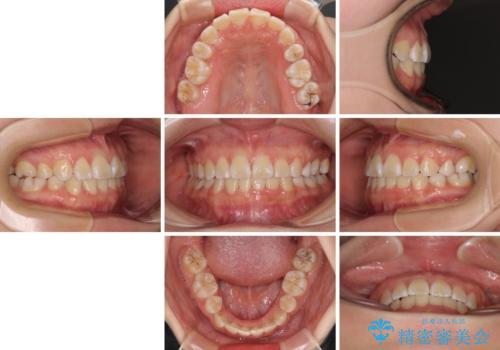

重度叢生と埋もれた奥歯 8本を抜歯したワイヤー矯正

親知らずの抜歯により埋もれた奥歯周辺の歯肉が切除され、矯正装置が装着できるようになりました。

奥歯の移動、特に下顎大臼歯の移動は時間がかかることが多く、3年以上の治療期間を想定していましたが、想像以上に動きがよく、2年強で終えることができました。